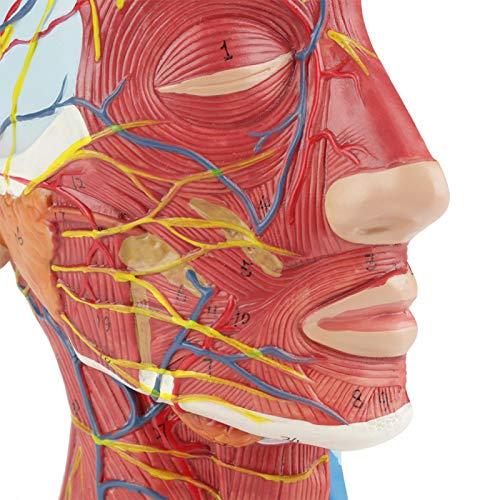

De ene kant toont interne structuur, de andere toont spier- en vasculaire structuur

De ene kant is voorzien van interne anatomie, de andere toont spier- en vasculaire anatomie. Zeer gedetailleerde getallen gemarkeerd, verdiepen het begrip van de structuur van de menselijke hersenen, vasculaire structuren. De gehele structuur is stevig gemonteerd op een kunststof basis, gemakkelijk te observeren. Het model is gemaakt van PVC-kunststof, dat corrosiebestendig, licht is en een hoge sterkte heeft. Toepasbaar op scholen, ziekenhuis, lichamelijke gezondheidsonderwijs, kan als leerhulpmiddel worden gebruikt.

Rode lijn: Artery

Blauwe lijn: Ader

Gele lijn: Zenuw

De ene kant toont interne structuur, de andere toont spier- en vasculaire structuur